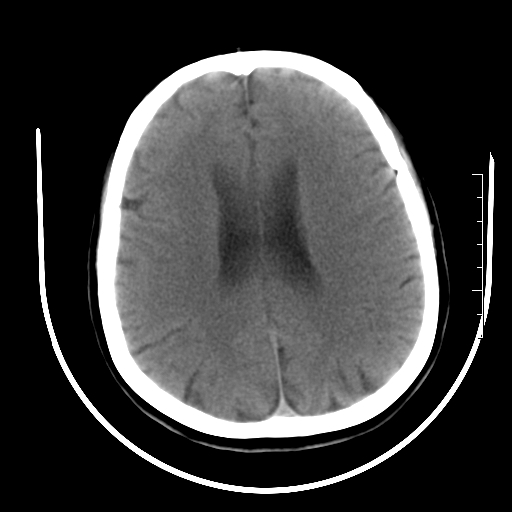

标题: CT27880:f、55y,头痛。 [打印本页]

标题: CT27880:f、55y,头痛。

考虑左侧顶部镰旁脑膜瘤;建议行ct增强扫描检查。

考虑左侧顶部镰旁脑膜瘤,建议行ct增强扫描检查。

考虑左侧顶部镰旁脑膜瘤;建议行ct增强扫描检查

大脑镰旁脑膜瘤可能,建议增强或mri

左侧顶部镰旁脑膜瘤,增强